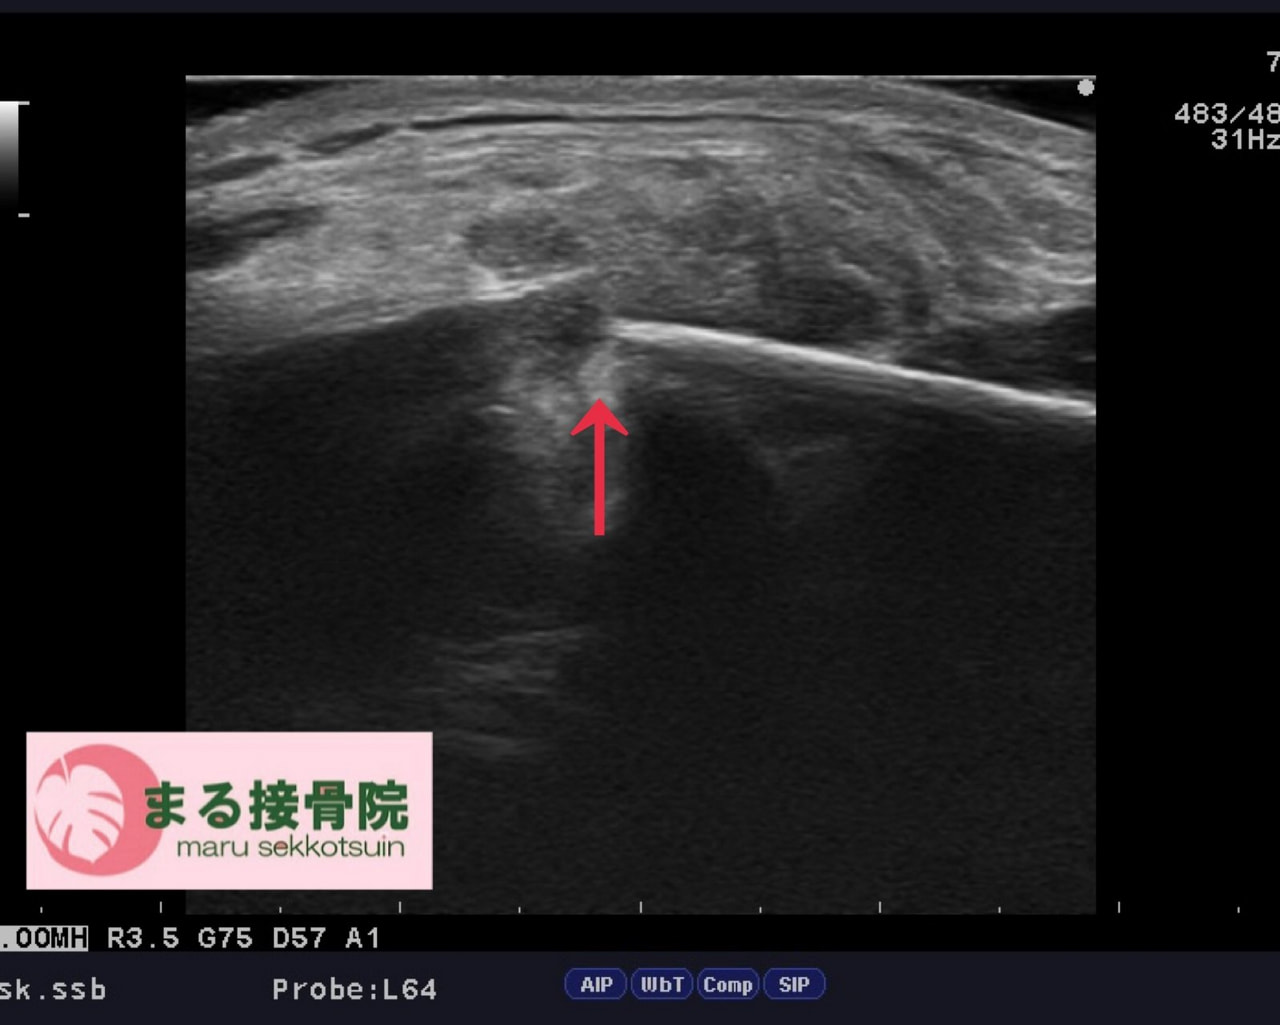

すぐにエコー検査を実施した結果、**「鎖骨骨折」**が確認されました。

骨折部位の形状から、自然な骨癒合を待つより手術による固定のほうが早期回復につながる可能性が高いと判断。

提携の整形外科にレントゲン検査を依頼し、結果的に手術適応となりました。